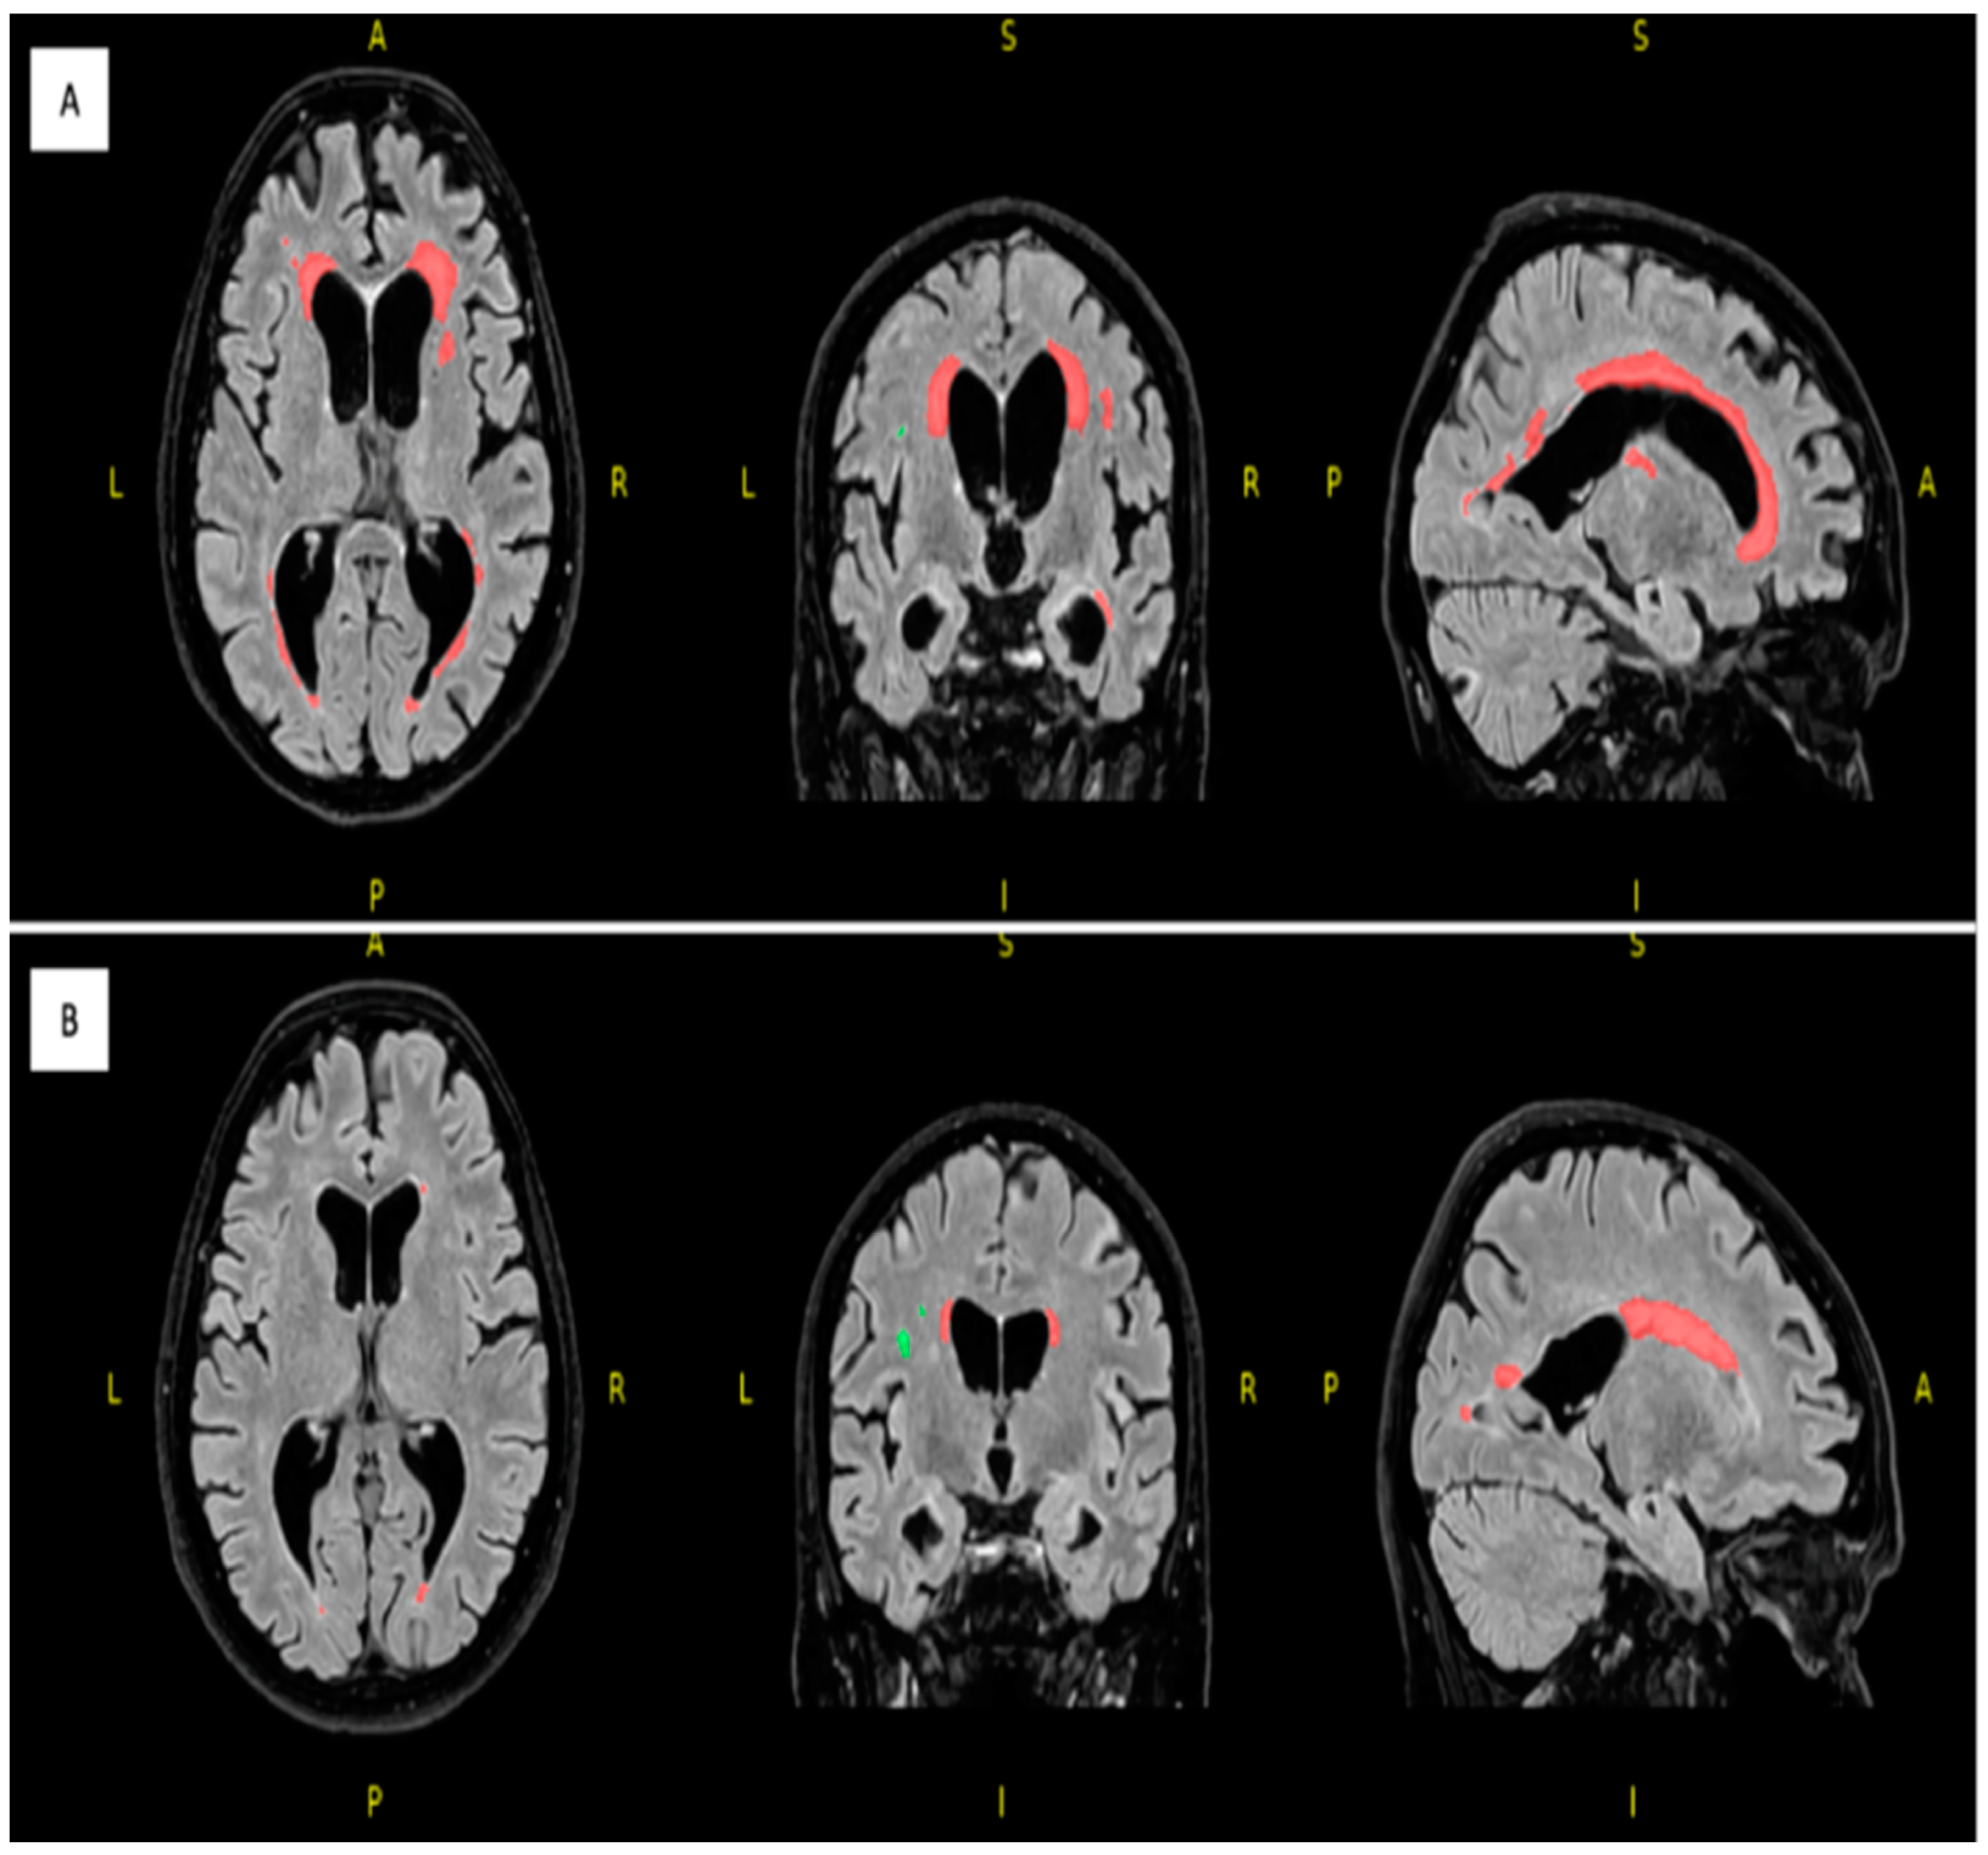

| Variable | Unaffected Twin | Affected Twin |

|---|---|---|

| Total lesions count | 24 | 36 |

| Total lesions volume (cm3) | 3.9192 | 30.0650 |

| Periventricular lesions count | 9 | 8 |

| Periventricular lesions volume (cm3) | 3.3902 | 29.4052 |

| Deep white lesions count | 12 | 17 |

| Deep white lesions volume (cm3) | 0.3136 | 0.3823 |

| Juxtacortical lesions count | 2 | 8 |

| Juxtacortical lesions volume (cm3) | 0.0362 | 0.2238 |

| Infratentorial cerebellar lesions count | 1 | 2 |

| Infratentorial cerebellar lesions volume (cm3) | 0.1793 | 0.0403 |

| Infratentorial medullary lesions count | 0 | 1 |

| Infratentorial medullary lesions volume (cm3) | 0 | 0.0132 |

| Volumes | Unaffected Twin | Affected Twin |

| Total white matter volume (cm3) | 403.59 | 387.12 |

| Total gray matter volume (cm3) | 664.13 | 623.45 |

| Total brainstem volume (cm3) | 20.34 | 16.14 |

| Frontal lobe volume (cm3) | 168.08 | 155.58 |

| Temporal lobe volume (cm3) | 103.83 | 103.51 |

| Parietal lobe volume (cm3) | 97.28 | 89.20 |

| Occipital lobe volume (cm3) | 80.16 | 76.79 |

| CSF Volume | Unaffected Twin | Affected Twin |

| Total CSF volume (cm3) | 220.89 | 272.12 |

| Inferior lateral ventricle volume (cm3) | 4 | 7.30 |

| Lateral ventricle volume (cm3) | 64.49 | 94.48 |

| 3rd ventricle volume (cm3) | 2.93 | 3.85 |

| 4th ventricle volume (cm3) | 3.55 | 5.27 |

| External CSF volume (cm3) | 145.92 | 161.23 |